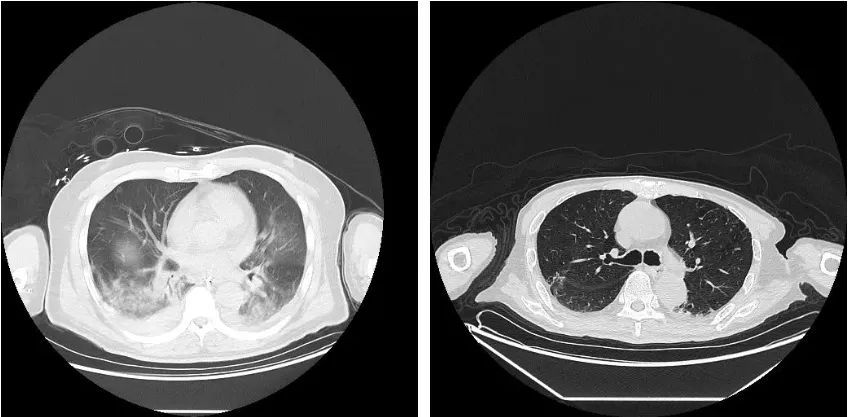

图片:患者前后肺部CT对比